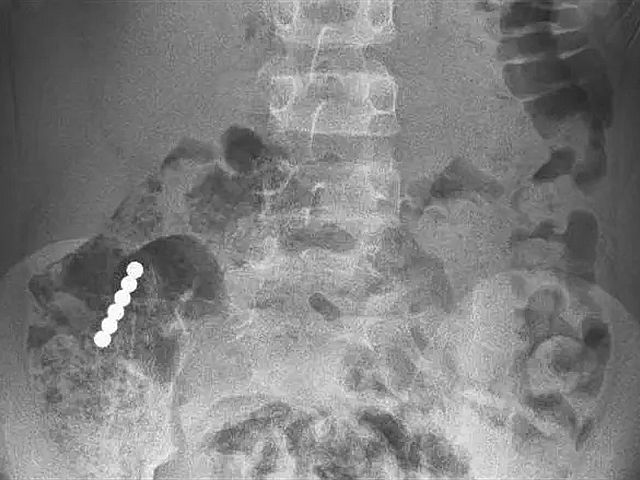

По словам доктора Самеха Татура, специалиста отделения детской и подростковой гастроэнтерологии, в больницу мальчик поступил в хорошем состоянии, у него не было ни рвоты, ни болей. В приемном покое ребенку сделали рентгеноскопию, показавшую несколько небольших магнитов, слипшихся в цепочку и находящихся в районе тонкого кишечника мальчика.